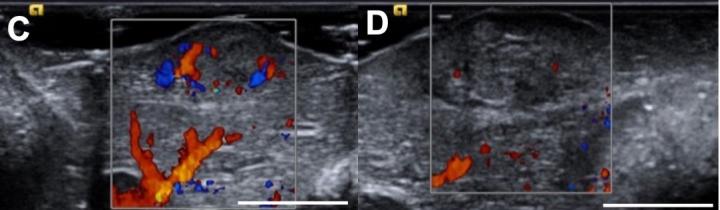

A liquid formulation can kill swathes of liver cancer cells and potentiate chemotherapy treatments, according to a study conducted in mice, rabbits, pigs and human tumor samples. The liquid could offer clinicians a safer and cheaper "bridge" to keep tumors in check in patients waiting for life-saving liver transplants. Chemotherapy remains the treatment of choice for patients with hepatocellular carcinoma (HCC), but these drugs have not made a major impact on five-year patient survival rates, which remain dismally low at around 9%. However, research has shown that liver transplantation can drastically improve outcomes in patients, raising 5-year survival rates to approximately 80%. Securing a liver transplant is therefore a major priority for clinicians and patients with early-stage disease, but organs are often difficult to find. In the meantime, clinicians keep tumors in check with local techniques such as thermal ablation - a procedure that vaporizes cancer cells with heat - but these approaches are resource-intensive, cannot be applied to all tumors, and can damage surrounding tissues. Hassan Albadawi and colleagues designed an alternative ablation technique based on an ionic liquid named LATTE, which can deliver both ablating agents and chemotherapy drugs directly into tumors. The team found that injections of LATTE shrank tumors either alone or in combination with the chemotherapy drug doxorubicin in rat and rabbit models of HCC, and rapidly killed cancer cells in 12 resected human tumors. "We anticipate that the safety profile of LATTE, its low cost, its simplicity of use, and the flexibility to repeat the procedure will make this [technique] appealing to physicians," the authors say.